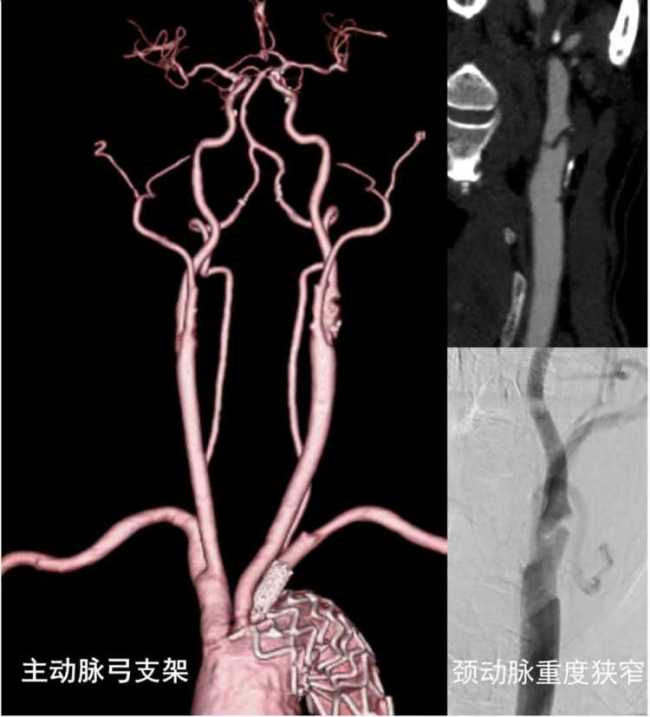

闵老伯曾因频发脑梗接受过主动脉弓支架治疗,这使得他无法再接受常规的治疗方法。于是他来到上海交通大学医学院附属仁济医院南院区求诊。神经外科团队联合超声医学科、麻醉科和手术室等多学科合作,采用国际前沿技术——颈动脉血运重建术,绕过主动脉弓,为复杂缺血性脑血管疾病患者进行微创手术。

颈动脉狭窄是缺血性脑卒中的常见病因之一,当狭窄程度超过70%时,脑梗死的风险显著升高。闵老伯的颈动脉狭窄超过90%,伴有溃疡形成,导致他频繁发生脑梗。然而,由于他之前在主动脉弓内进行过支架治疗,血管解剖结构发生变化,常规的颈动脉支架手术无法实施。

专家们决定采用最新的颈动脉血运重建术。这种技术通过颈部显露颈动脉,直接绕过主动脉弓,并利用特殊装置实现持续高速逆向血流,从而减少斑块脱落的风险。手术当天,超声医学科副主任医师夏建国对颈动脉手术区域进行了精准定位。随后,赵兵和戴炯两位主任医师凭借娴熟的操作技巧,顺利完成了手术。术后,闵老伯感觉头晕症状明显缓解,右侧肢体的麻木无力症状也消失了,脸上露出了久违的笑容。